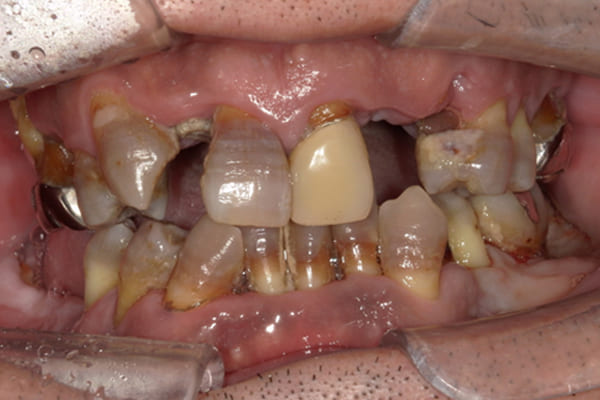

上前歯はブリッジの差し歯により根が折れ炎症を起こしお痛みのある状態でした。

原因は長期使用により下の義歯の歯が削れたことにより、下前歯が上前歯を突き上げ強い力が加わっていたことが根本的な原因と考えられます。

治療前は、奥歯が下がり、かみ合わせが乱れています。適切な入れ歯はそのままのかみ合わせで義歯を作るのではなく治療後のように、前歯から奥歯までのラインが真っすぐ揃った、かみ合わせの面を適切に付与し、よく咬め、残りの歯に負担がかからないかみ合わせとしました。

根のみの7本は虫歯にもなっており歯肉は腫れあがっています。

残りの歯もレントゲンで重度の歯周炎によりぐらぐらな状態でした。